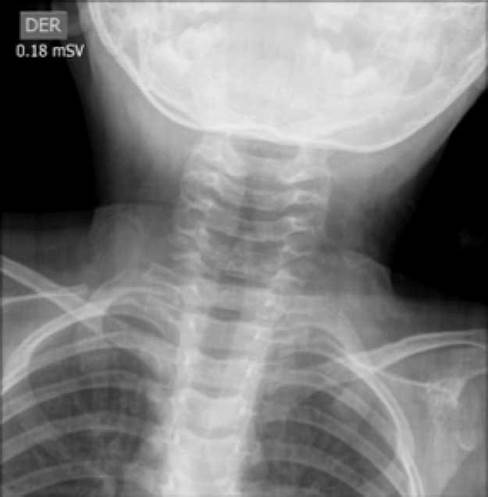

Chest and neck radiographs were requested for an initial approach (Figure 1 and 2). The radiology service found a steeple sign that suggested laryngeal croup in the anteroposterior (AP) projection of the second image. Likewise, the lateral projection shows an object that could be a foreign body. Chest X-ray was normal.

Anteroposterior radiograph of the neck. Steeple sign.

Figure 1: Anteroposterior radiograph of the neck. Steeple sign.

Source: Own elaboration based on the data obtained in the study.